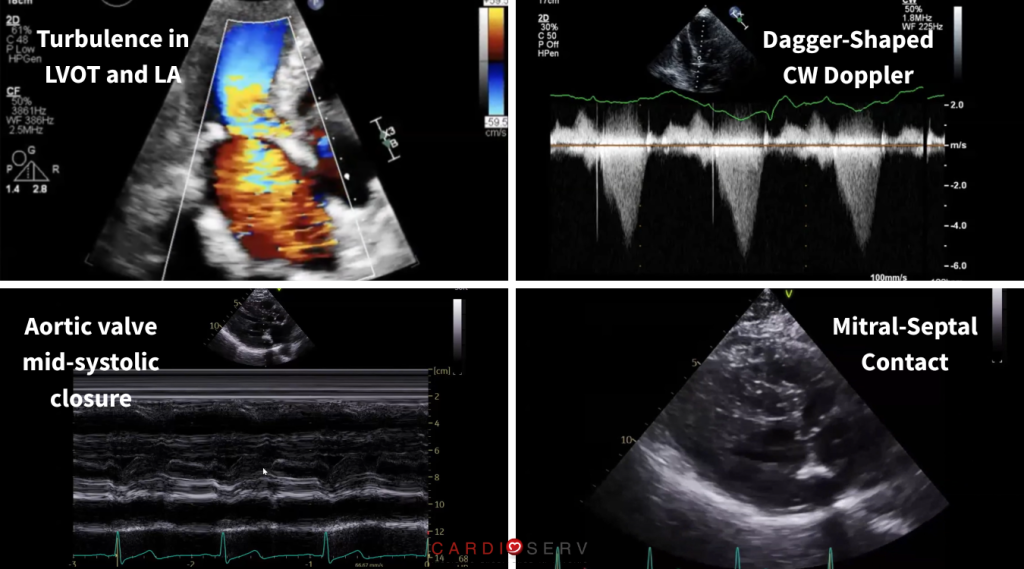

Clues You Should Not Ignore in Obstructive HCM

There are several subtle findings that can support the diagnosis of obstructive HCM:

- Turbulence in two directions (LVOT and left atrium)

- Late-peaking (dagger-shaped) CW Doppler waveform in the LVOT

- Mitral-septal contact

- Aortic valve mid-systolic closure (M-mode notch)

These are not isolated findings, they are pieces of a larger picture.

When they come together, they tell a much clearer story.